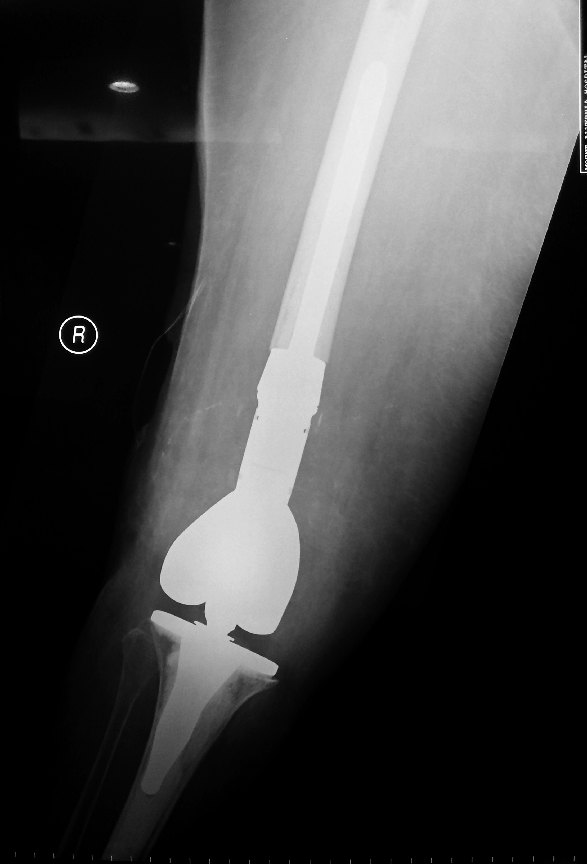

Decision to revise the knee replacement using a rotating hinge knee from Zimmer was made.

During surgery, the fractures distal femur piece with the femoral implant was excised.

The tibial implant was also extracted.

A Zimmer Segmental System Knee was implanted.

The Zimmer® Segmental System is designed to address patients with significant bone loss often found in oncology, trauma, and/or multiple revisions.

It consisted of distal femoral components, a one-piece hinge post, tibial articular surfaces, male-female and male-male segments, fluted straight and bowed stems, and stem collars with either Trabecular Metal™ Material or a smooth titanium surface.

This surgery allowed immediate stability of the knee. The patient was able to get up to stand and walk once the surgical pain was better.